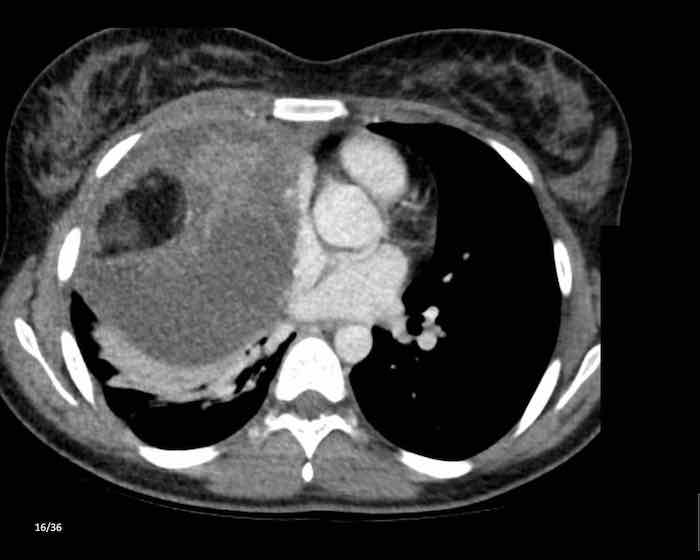

Các hình ảnh này của một phụ nữ 65 tuổi có tiền sử mắc bệnh Graves, một rối loạn tự miễn liên quan đến tình trạng cường chức năng tuyến giáp.

CT được thực hiện vì lý do ho ra máu.

Hình ảnh

Có một tuyến ức to lớn, cồng kềnh chứa mô mỡ đại thể.

Đây là hình ảnh điển hình của tăng sản tuyến ức.

Tăng sản tuyến ức trong bệnh Graves có liên quan đến tình trạng dư thừa hormone tuyến giáp và kháng thể kháng thụ thể thyrotropin.

Tình trạng này thường cải thiện sau khi điều trị thành công bệnh Graves.